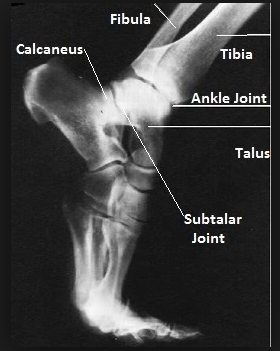

1) 정상 보행으로 발아치가 있을때

2) tiptoe 까치발로 설 때

- 까치발로 서면 경골 - 거골 - 주상골 - cuneiform bone - metatsal bone